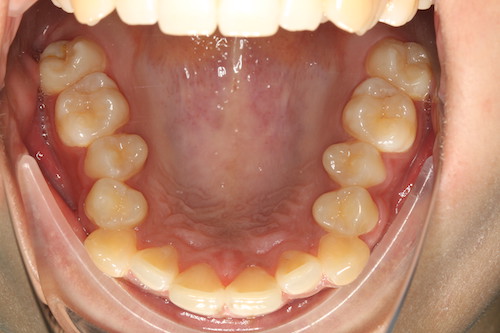

До